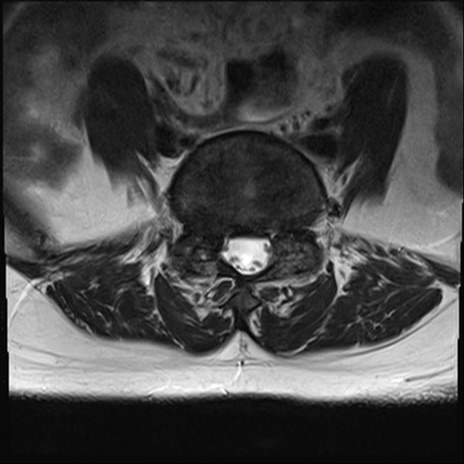

【整形】TIPS症例4 腰椎MRI T2WI(横断像)

腰椎MRI

横断像と矢状断像